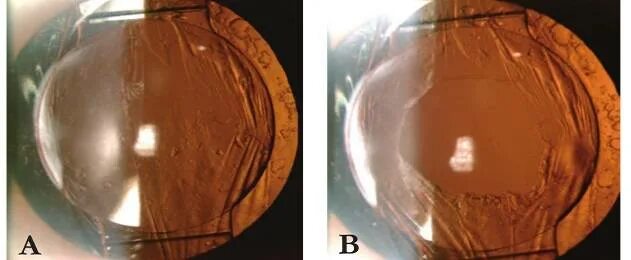

Катаракта глаза после операции замена хрусталика